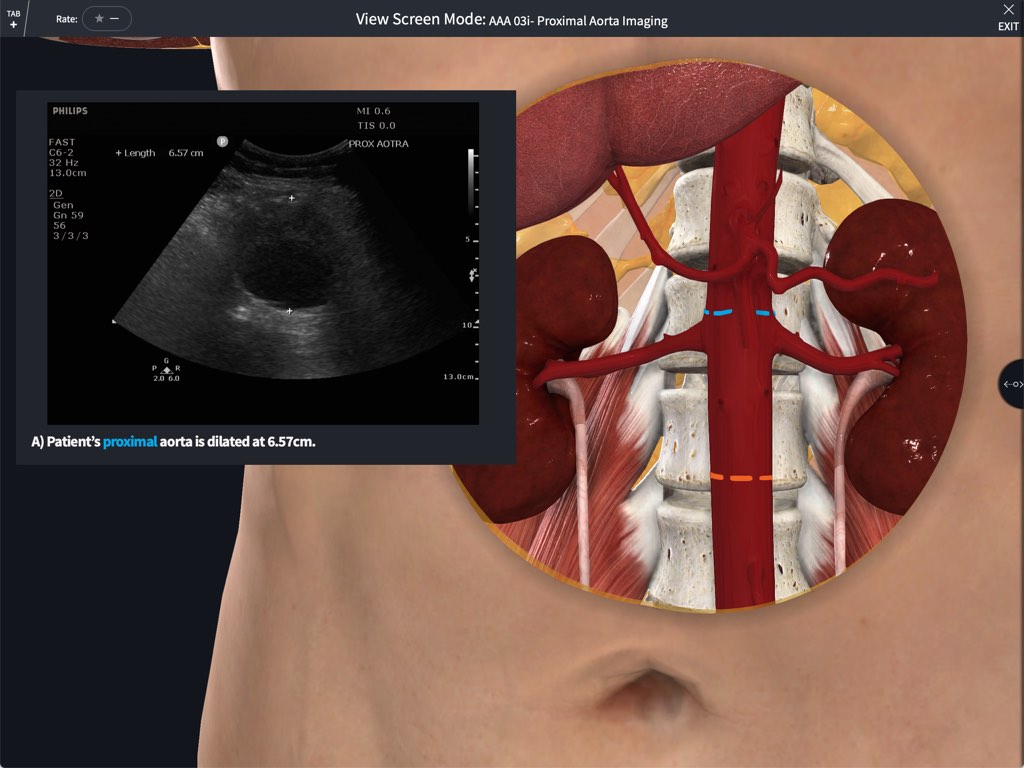

Point of Care Ultrasound